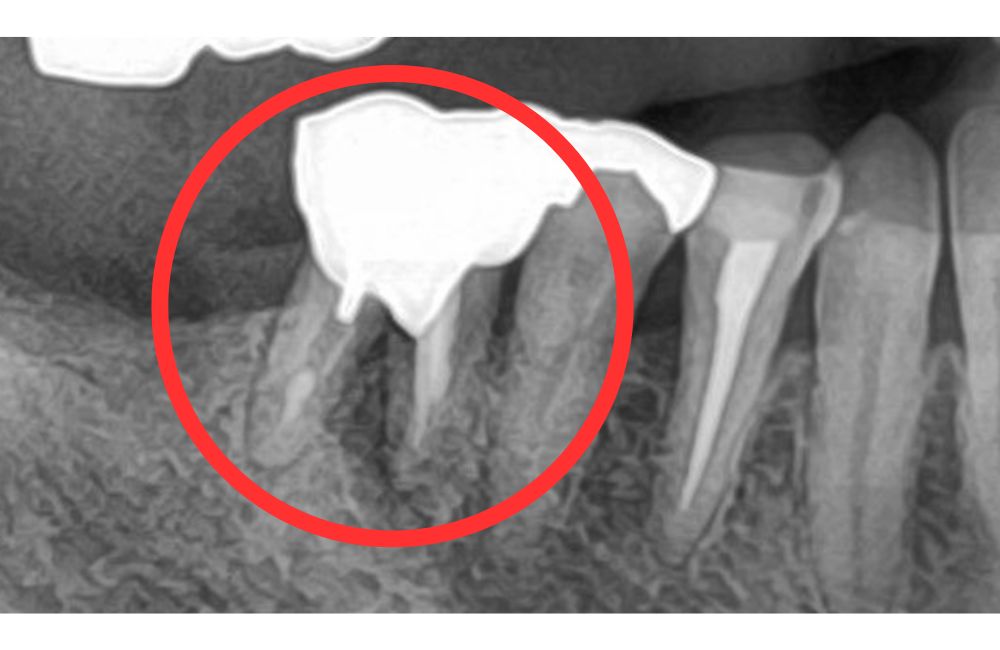

治療前の口腔内写真とレントゲン写真

かみ合わせの力で割れていました。